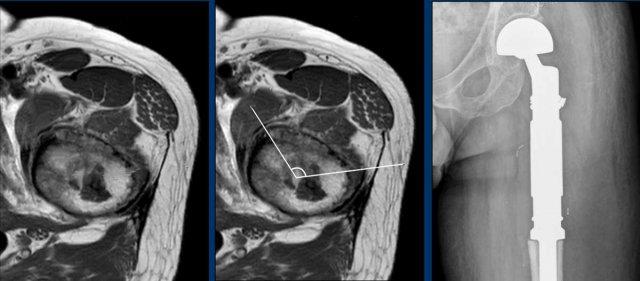

Có một tổn thương tiêu xương, dạng giãn rộng ở thân xương đùi phải đoạn gần.

Có hiện tượng dày vỏ xương nhẹ lân cận mà không có phản ứng màng xương.

Không thấy chất nền sụn rõ ràng trên phim X-quang này.

Kết luận

Chẩn đoán phân biệt bao gồm sarcoma sụn, loạn sản xơ, u lympho, di căn và u tương bào.

Chụp CT không tiêm thuốc cản quang có thể giúp phát hiện các vôi hóa chất nền sụn nhỏ trong trường hợp này. Tuy nhiên, chúng tôi đã tiến hành thẳng vào MRI.

Hình ảnh

Hình ảnh T1W cho thấy sự thay thế tủy xương.

Hình ảnh T2W cho thấy phản ứng màng xương

và phù tủy xương quanh tổn thương.

Bản thân khối u tăng tín hiệu và

có dạng nốt.

Hình ảnh T1W FS sau tiêm Gd cho thấy

hình thái ngấm thuốc dạng vòng và cung.

Tất cả những phát hiện này phù hợp với một khối u sụn, và rất nghi ngờ là u sụn ác tính độ II hoặc cao hơn.

Tại trung tâm chuyên khoa tuyến ba về sarcoma xương của chúng tôi, chúng tôi không thực hiện sinh thiết đối với các khối u sụn này, vì điều này có thể gây ra sai số lấy mẫu do tính không đồng nhất bên trong khối u.

Bạn có thể vô tình sinh thiết vào phần lành tính hơn của khối u và đánh giá thấp độ mô học.

Các khối u sụn được biết đến với khả năng gieo rắc theo đường sinh thiết.

Continue with the postoperative

X-rays…..

Điều trị bao gồm cắt bỏ khối xương đùi gần và tái tạo bằng nội khớp giả.

Pathology confirmed a chondrosarcoma grade II.

Chondrosarcoma độ II và độ III không thể phân biệt dựa trên hình ảnh học.

Đây là chẩn đoán được thực hiện dựa trên mô bệnh học.

Do đó, chúng tôi gọi các tổn thương như vậy là “độ II hoặc cao hơn” trong báo cáo chẩn đoán hình ảnh của chúng tôi.